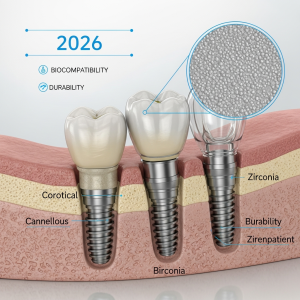

Avantajele Zirconiului pe Implanturi Bicorticale în 2026

Implanturile dentare bicorticale, ancorate în osul bazal dens, reprezintă o soluție avansată. În 2026, utilizarea zirconiului pentru aceste implanturi aduce beneficii semnificative, confirmate de studii recente.

Biocompatibilitate și Integrare Ososă

Zirconiul este hipoalergenic și prezintă o afinitate excepțională pentru țesutul osos. Acest lucru minimizează riscul de reacție adversă și sprijină osteointegrarea stabilă, esențială pentru succesul pe termen lung al implantului bicortical.

Rezistență Mecanică Superioară

- Rezistă la presiunile puternice din zona bazală.

- Risc extrem de scăzut de fractură sau fisurare.

- Durabilitate dovedită în situații cu volum osos redus.

Estetică și Stabilitate Cromatică

Culoarea alb-dinților a zirconiului asigură un rezultat estetic natural, fără decolorări în timp. Acest aspect este crucial pentru zona frontală, chiar și atunci când implantul este plasat profund.

Reducerea Riscului de Periimplantită

Suprafața netedă și netezibilă a zirconiului împiedică aderența bacteriană mai eficient decât titanul. Studiile indică o rată mai mică de complicații inflamatorii periimplantare.

Potrivire pentru Pacienții cu Sensibilități

Este materialul de elecție pentru pacienții cu intoleranțe sau sensibilități cunoscute la metale, oferind o alternativă sigură și eficientă.

În concluzie, combinarea dintre designul bicortical și proprietățile avansate ale zirconiului definește un standard înalt în implantologia modernă, cu rezultate predictibile și durabile.